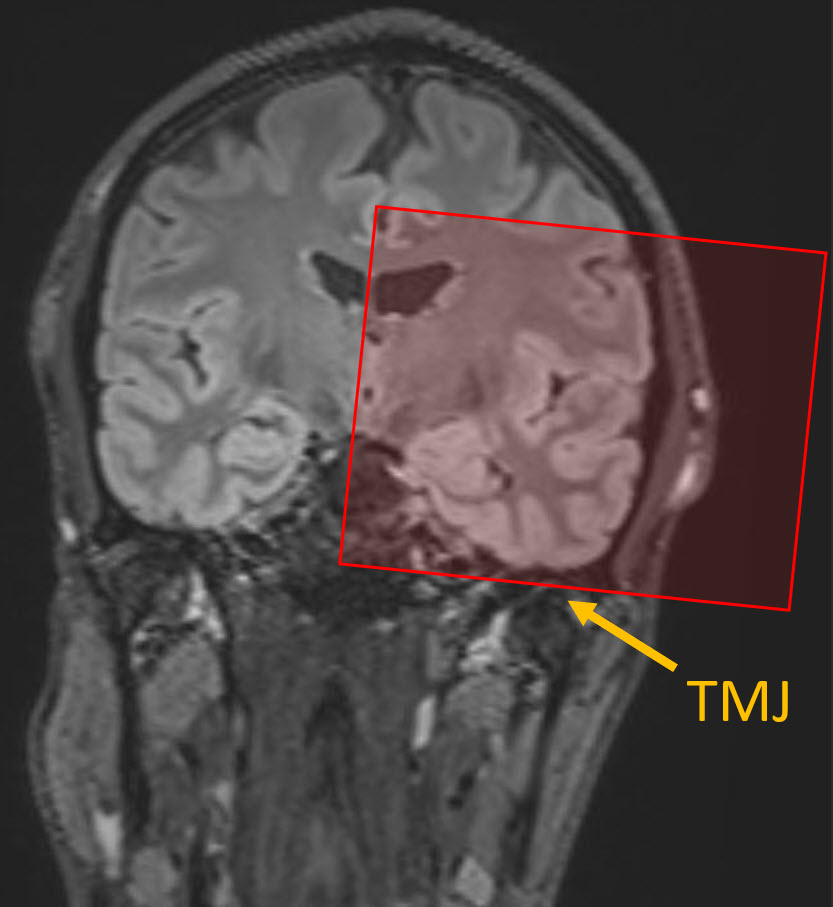

• Inferior-most slice in stack should be centered on the TMJ (see pic below).

Coronal FLAIR image showing anatomic coverage for this MRI seqeunce.